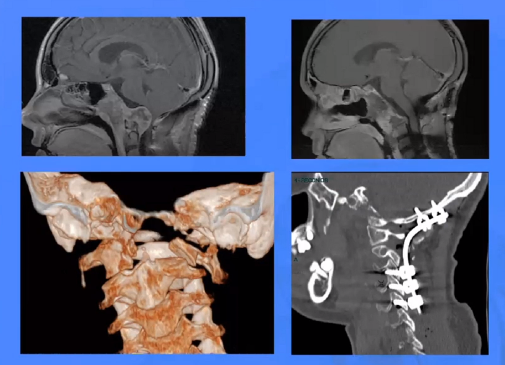

▼这是几年前做的一个手术,先把鼻中隔先推开,然后推开那些正常的组织,这里磨掉枕髁,暴露舌下神经管。虽然很具有挑战性,但是手术做得还是不错的,我们对病人进行了长期的随访,因为我们把所有的就是切开的软组织都复位了,所以看起来还可以,经过内固定以后,病人的颅颈交界区是很稳定的。